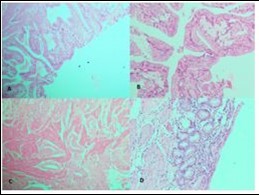

Figure 3.Photomicrograph showing A, Low power view of Adenocarcinoma Gall bladder; B, High power view shows attempted gland formation with moderate pleomorphismmoderately differentiated adenocarcinoma Gall Bladder; C, Low power view of Papillary carcinoma GB; D, High power view showing papillae with fibrovascular cores lined by malignant cells- Papillary carcinoma GB (H&E)

Photomicrograph showing A, Low power                   view of Adenocarcinoma Gall bladder; B, High power view shows attempted gland formation with moderate                  pleomorphismmoderately differentiated adenocarcinoma Gall Bladder; C, Low power view of Papillary carcinoma GB; D, High power view showing papillae with fibrovascular cores lined by malignant cells- Papillary carcinoma GB (H&E)